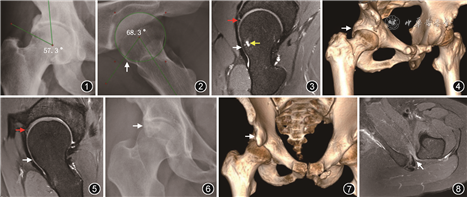

X线平片是FAI的首选影像学检查方法。X线平片可以显示FAI的骨性结构异常,常用的投照体位为标准骨盆正位片和股骨近端侧位,后者包括蛙式位、Dunn45°位或穿台位。在标准骨盆正位片上,中心边缘角超过39°和髋臼指数小于0°提示普遍性髋臼过度覆盖(图1),交叉征或8字征提示髋臼前壁过度覆盖或髋臼后倾伴后壁发育不良,后壁征提示髋臼后壁过度覆盖,坐骨棘征提示髋臼后倾。在侧位片上可以测量α角和股骨颈偏距,α角>55°(图2)、股骨颈偏距<10 mm以及偏距率(股骨颈偏距与股骨头直径的比值)<0.17均提示存在Cam样畸形[3]。FAI的患者常会在股骨头颈交界处前上方出现皮质下方囊性灶,直径一般小于15 mm,边缘可见硬化边,称为股骨颈疝窝或滑膜疝,MRI上显示更加清晰(图3),一般认为其与Cam型FAI有关[4]。髋臼小骨是由于股骨近端与髋臼反复撞击引起髋臼外侧缘的应力骨折所致,多见于Pincer型FAI[5]。

X线平片的主要缺点是测量结果受投照体位影响较大,投照体位不标准可能会导致测量结果的偏差。CT显示细微骨质结构的能力更强,可以去除体位因素的影响,三维重建技术可以更加直观地显示髋臼和股骨近端的骨性结构异常(图4),测量的结果也更加准确。

MRI和MR关节造影除了可以显示骨性结构异常以外,还可以显示髋臼盂唇撕裂及关节软骨损伤[6]。对于怀疑FAI的患者的MRI或MR关节造影检查要求单髋扫描,扫描方位主要包括冠状面、横断面、矢状面及平行于股骨颈长轴的斜轴面,而放射状扫描可以减少常规MRI扫描序列产生的图像扭曲和部分容积效应,提高显示髋臼盂唇撕裂和关节软骨损伤的能力[3]。下肢牵引MR关节造影可以使关节液或对比剂进入股骨头与髋臼之间的间隙,提高显示关节软骨损伤的能力[7]。

髋臼盂唇为附着于髋臼边缘的纤维软骨,正常呈三角形,表面光滑,在所有序列上均呈低信号。髋臼盂唇的主要功能是增加髋臼深度和关节稳定性,封闭关节内的滑液,减少压力,保护关节软骨。急性或亚急性髋臼盂唇撕裂在T2WI或中等加权像上表现为髋臼盂唇内高信号达髋臼盂唇表面,强度接近或达到关节液的信号,而在MR关节造影上则表现为对比剂进入到盂唇内。慢性髋臼盂唇撕裂由于撕裂局部出现肉芽组织或者滑膜组织阻止关节液或对比剂进入撕裂的盂唇内而在MRI或MR关节造影上均呈中等或稍高信号。髋臼盂唇撕裂分为两型,1型撕裂发生于盂唇-关节软骨移行部,由关节内剪切力引起,为盂唇自关节软骨表面分离,撕裂垂直于关节面;2型撕裂发生于盂唇实质内,由作用于盂唇表面的压缩力引起,为盂唇实质内的线样裂隙[10]。Cam型FAI引起的盂唇撕裂多位于髋臼前上象限的盂唇-关节软骨移行部(图5),Pincer型FAI引起的盂唇撕裂多位于髋臼的前上及后下象限。盂唇退变表现为盂唇实质内未达盂唇表面的稍高信号,而盂唇表面毛糙、不规则则提示为盂唇磨损。全层厚盂唇撕裂常会导致盂唇旁囊肿形成。此外,盂唇根部与关节软骨之间偶尔会出现一种发育变异,称为盂唇下沟或盂唇下隐窝,需要与盂唇撕裂鉴别。盂唇下沟或盂唇下隐窝为盂唇与相邻髋臼部分分离,仅达关节面,一般形态规则,边缘光整,局部盂唇及邻近组织多正常[3]。

SSI的X线平片表现常不明显,骨盆正位片上可出现髂前下棘肥大、髂前下棘陈旧撕脱骨折、股直肌直头内钙化、髂前下棘游离缘的位置低于髋臼眉弓(图6)。此外,突出的髂前下棘可能会在骨盆正位片上形成交叉征,造成髋臼后倾的假象。假侧位和Dunn45°位X线平片有助于显示突出的髂前下棘。此外,在股骨颈远侧部前缘还会出现撞击形成的囊变。有文献认为股骨颈远侧部出现Cam样畸形及撞击征象提示与SSI有关[13]。

骨盆CT三维重建可以更加清晰直观地显示髂前下棘的形态和位置,有助于明确诊断及术前评估(图7)。

IFI典型的MRI表现是IFS和QFS变窄,股方肌受挤压变形,急性期表现为肌肉水肿,脂肪抑制T2WI或STIR序列上呈高信号(图8),慢性期表现为肌肉体积减小和/或脂肪浸润,后者在T1WI及T2WI上均呈高信号。此外,还可出现坐骨结节和股骨小粗隆的骨髓水肿及皮质下囊变、局部滑囊积液、腘绳肌腱撕裂及髂腰肌止点周围水肿[14]。